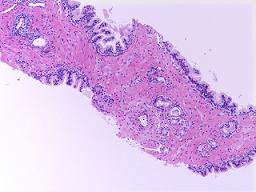

The Genitourinary (GU) pathology service at UMass Memorial Medical Center provides skilled interpretation of specimens from the prostate, urinary bladder, kidney and testis. Our GU  pathology section serves the UMass Memorial Medical Center and urology practices in Massachusetts and Connecticut. We have developed a novel molecular diagnostic technique combining cytology and fluorescent in situ hybridization (FISH) analysis, a cutting edge technology for the diagnosis of urothelial carcinoma. We utilize an array of immunohistochemical and molecular biological techniques in the evaluation of pathological diagnostic problems.

pathology section serves the UMass Memorial Medical Center and urology practices in Massachusetts and Connecticut. We have developed a novel molecular diagnostic technique combining cytology and fluorescent in situ hybridization (FISH) analysis, a cutting edge technology for the diagnosis of urothelial carcinoma. We utilize an array of immunohistochemical and molecular biological techniques in the evaluation of pathological diagnostic problems.

Our major research focus is the identification and validating novel biomarkers for diagnostic and prognostic use. Alpha-methylacyl-coenzyme A racemase (AMACR/P504S), a molecular diagnostic biomarker for prostate cancer that Dr. Jiang first described in 2001, now assists pathologists around the world accurately diagnose prostate cancer in prostate needle biopsies. Recently, we discovered IMP3, a new molecular marker that allows patients and cliniciansget an accurate prediction of the metastatic potential or progression of renal cell carcinoma and superficial bladder cancer.

Our major research focus is the identification and validating novel biomarkers for diagnostic and prognostic use. Alpha-methylacyl-coenzyme A racemase (AMACR/P504S), a molecular diagnostic biomarker for prostate cancer that Dr. Jiang first described in 2001, now assists pathologists around the world accurately diagnose prostate cancer in prostate needle biopsies. Recently, we discovered IMP3, a new molecular marker that allows patients and cliniciansget an accurate prediction of the metastatic potential or progression of renal cell carcinoma and superficial bladder cancer.